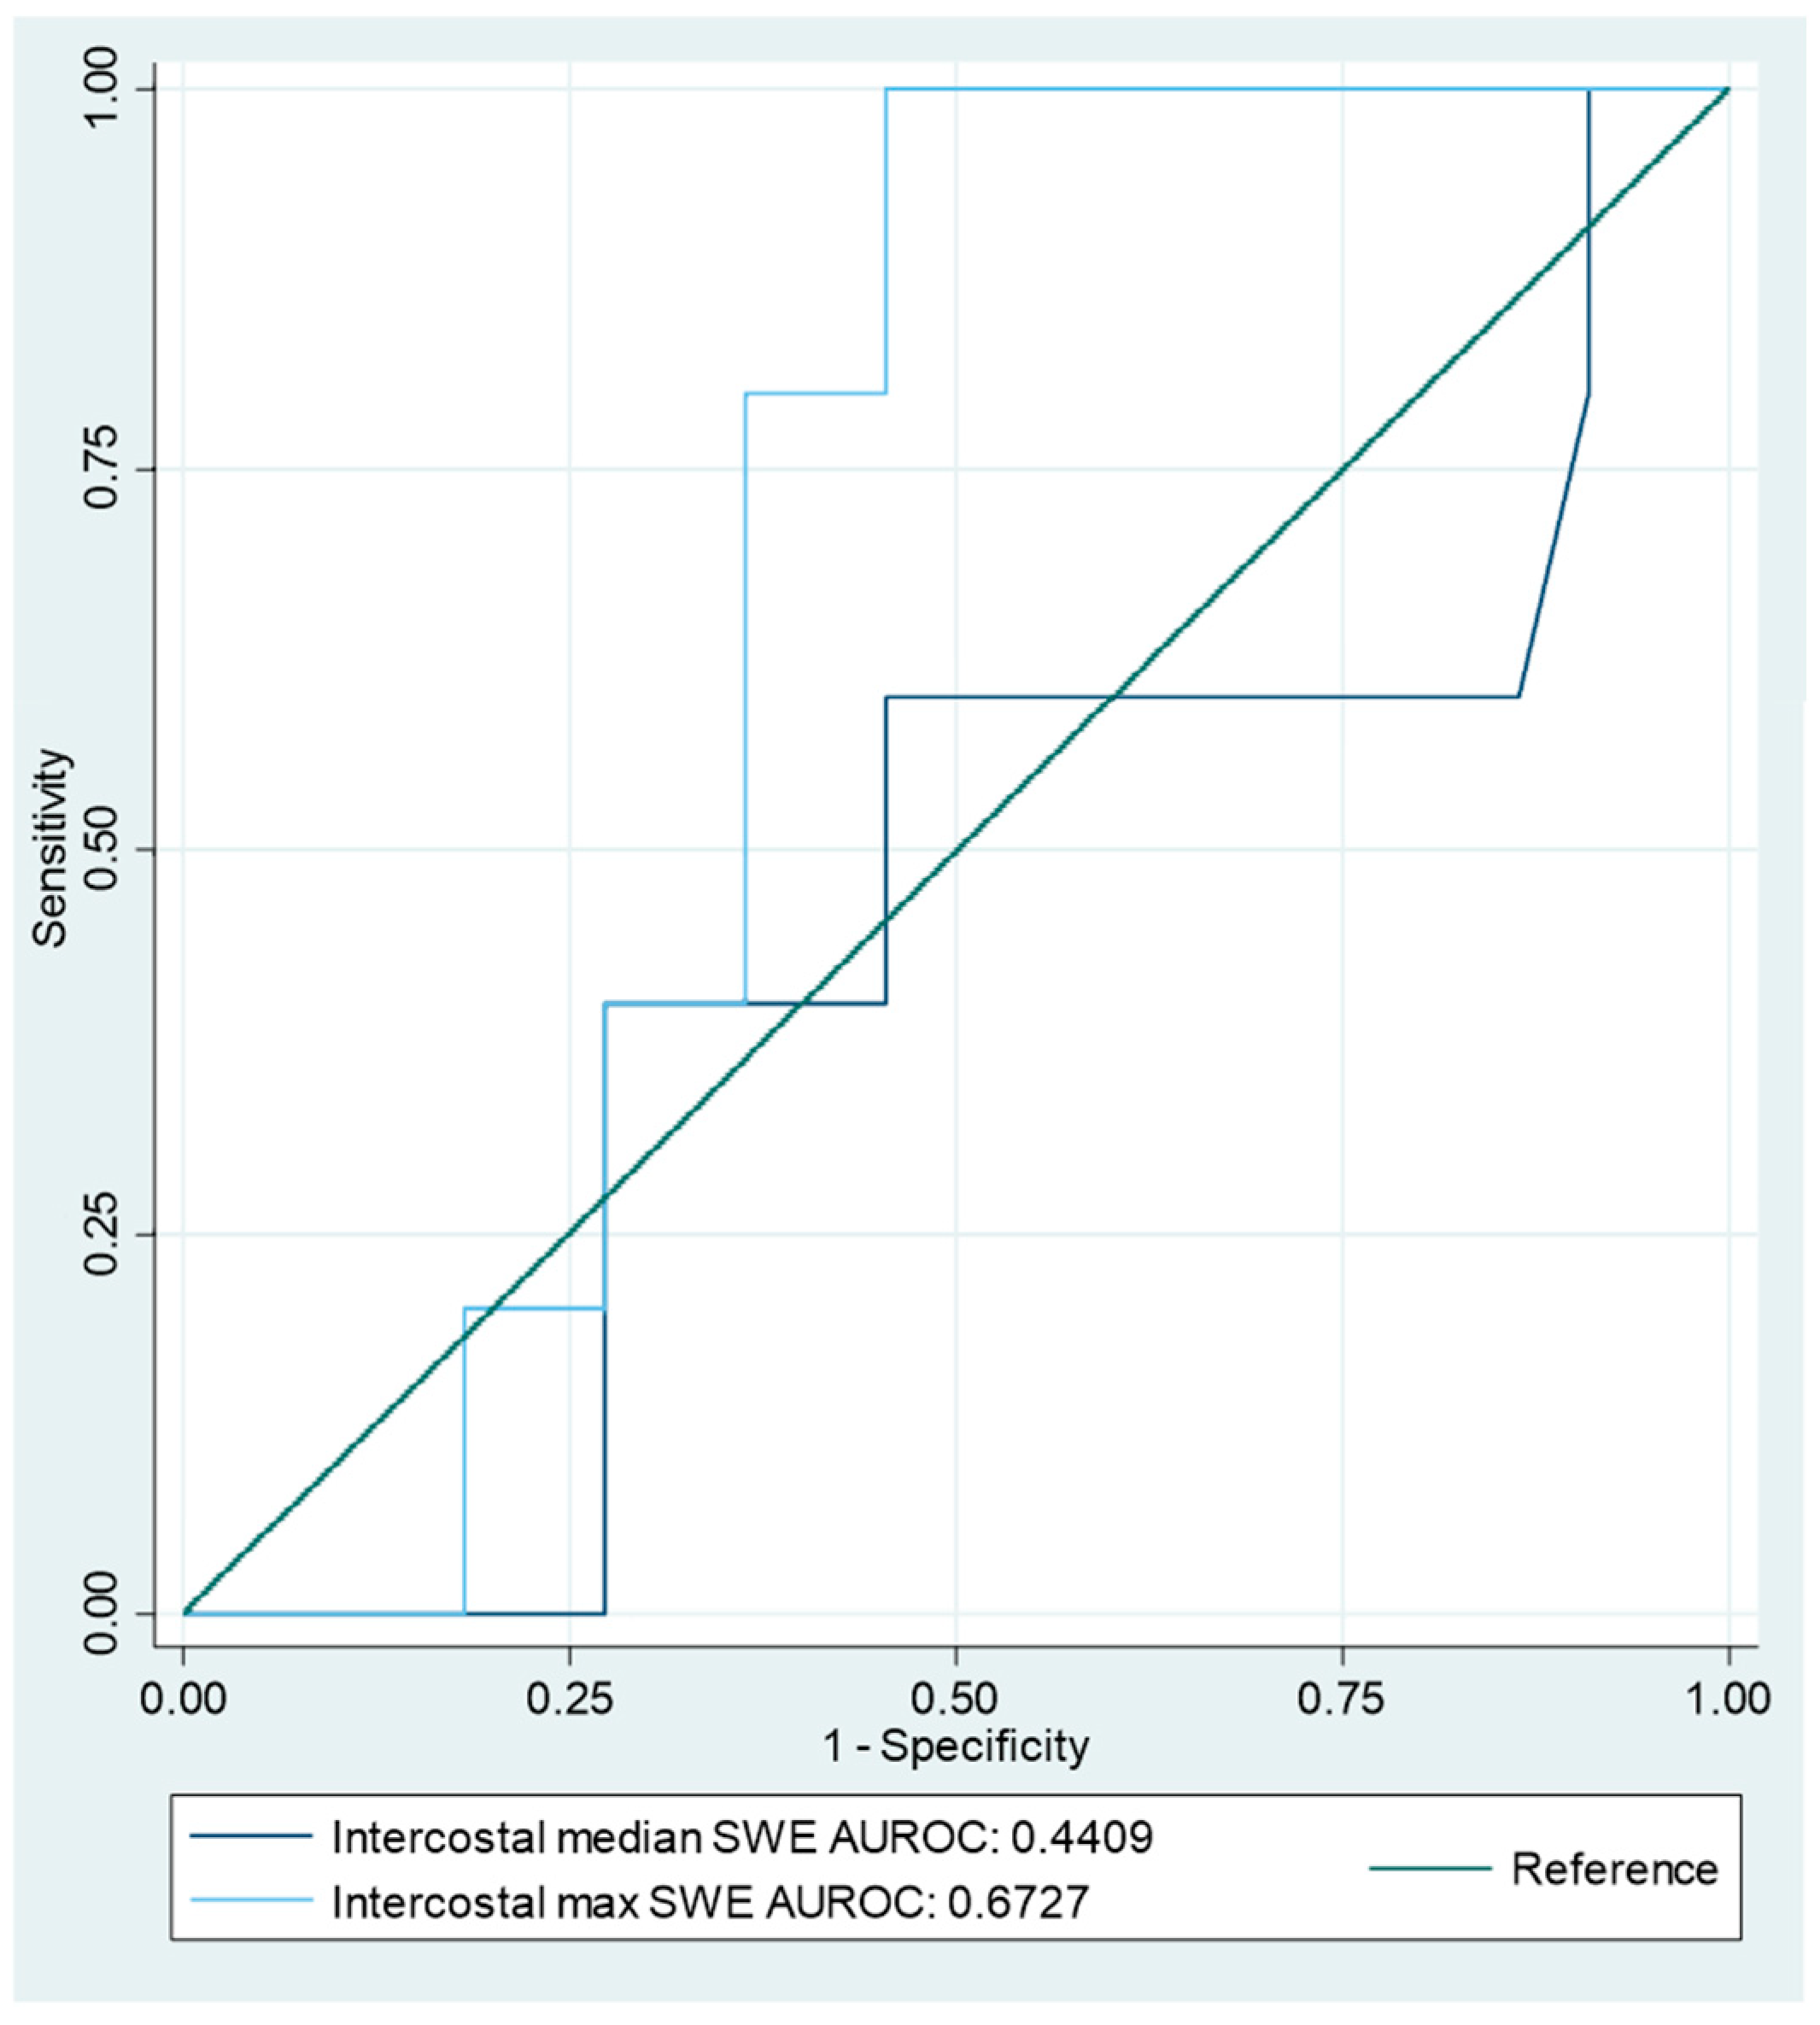

3.2. Shear Wave Elastography Findings

3.3. Structuring an SWE-Based Index Test

3.4. Diagnostic Accuracy of the Index Tests

| Intercostal velocity median | 5/22 | 1.68 | 60% (15–95%) | 55% (32–76%) | 0.57 | 0.145 | 23% (11–41%) | 86% (66–95%) | 1.32 (0.56–3.1) | 0.73 (0.23–2.29) | 56% (35–75%) |

| Intercostal velocity max | 2.01 | 100% (48–100%) | 59% (36–79%) | 0.77 | 0.545 | 36% (25–48%) | 100% | 2.44 (1.5–4) | 0 | 67% (46–84%) | |